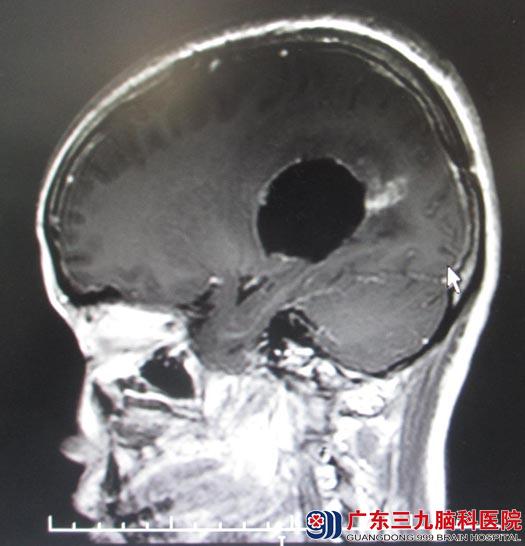

四月份曾在广东三九脑科行颅脑MR检查,示:右侧侧脑室三角区巨大占位性病灶,考虑肿瘤性病变。后入住综合神经外科,复查颅脑MR显示:1、右侧侧脑室三角区及周围巨大占位病灶,大小约7cm×9cm,考虑室管膜瘤、中枢神经细胞瘤或PNETs(原始性神经外胚层瘤)可能;2、右侧大脑镰下疝,右侧海马钩回疝,小脑扁桃体轻度下疝;3、空泡蝶鞍。肿瘤挤压对侧脑室,中线左移。